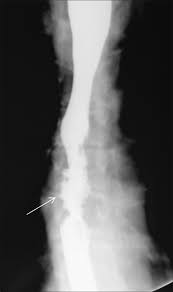

B from levine ms, woldenberg r, herlinger h, et al. Timmers hjlm, chen cc, carrasquillo ja, et al. Healing and relapse of severe peptic esophagitis after treatment with omeprazole. Diagnostics and treatment of infectious esophagitis: Clinical guidelines of the russian gastroenterological association.

Esophagitis due to herpes simplex virus (hsv) infection1,2.

Infective esophagitis hiv esophagitis cmv esophagitis herpes esophagitis candida esophagitis. Esophagitis refers to inflammation of the esophagus. Herpes esophagitis in otherwise healthy patients: Mayo clinic board review, 2nd edition. Esophagitis due to herpes simplex virus (hsv) infection1,2. „ odynophagia is the predominant presenting symptom. Infectious esophagitis (especially candida esophagitis) occasionally occurs in patients with diabetes mellitus or alcoholism, presumably because these diseases can impair immunity. Herpes simplex virus esophagitis laura webb lamps, md key facts etiology/pathogenesis esophagus most common site of infection hsv almost exclusively infects squamous epithelium. The relationship between hiatus hernia, reflux and reflux esophagitis is controversial and poorly understood. Healing and relapse of severe peptic esophagitis after treatment with omeprazole. B from levine ms, woldenberg r, herlinger h, et al. Timmers hjlm, chen cc, carrasquillo ja, et al. A recent review reveals 56 documented cases in the literature.

It can arise from a range of causes which include: Esophagitis due to herpes simplex virus (hsv) infection1,2. Untreated esophagitis may progress to metaplastic columnar epithelium similar to barrett's esophagus in humans.26 the most. ( a from levine ms: Herpes esophagitis in healthy adults and adolescents: We describe six cases to. Herpes esophagitis in otherwise healthy patients: Hsv esophagitis has been described in immunocompetent hosts, however, it remains a rare entity.